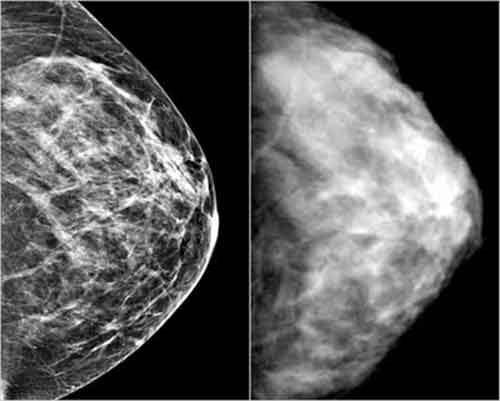

mammografia

Uno studio ha mostrato che lo screening mammografico non ha avuto impatti sulla mortalita’ per cancro al seno fra le donne svedesi che hanno fra 40 e 69 anni. La ricerca e’ stata condotta dall’Istituto Internazionale per la Prevenzione e la Ricerca francese ed e’ stato pubblicato sulla rivista “Journal of The National Cancer Institute”. Dal 1974, in Svezia, le donne di quella fascia d’eta’ sono state incluse in un programma di prevenzione del cancro alla mammella che ha offerto loro uno screening mammografico: la copertura del Paese ha raggiunto il suo picco nel 1997. Gli studiosi hanno allora cercato di capire in che modo questo sforzo si riflettesse sul tasso di mortalita’ per il cancro al seno.